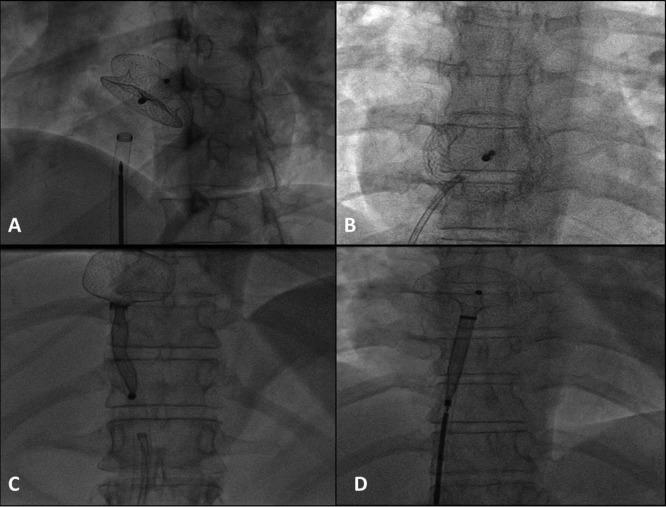

Tough, but not impossible - Retrieval of large atrial septal occluder devices embolized to left atrium.

Atrial septal defect (ASD) is a congenital heart defect that is being increasingly treated using percutaneous interventions. However, these techniques are not devoid of complications. One such complication is device embolization. Removal of such closure device poses tremendous risk and consequent complications both by percutaneous retrieval and surgical removal. Herein, we present two cases of ASDs that were closed using atrial septal occluder, but the devices were subsequently embolized into left atrium. These devices were then percutaneously retrieved without any further complication or injury.